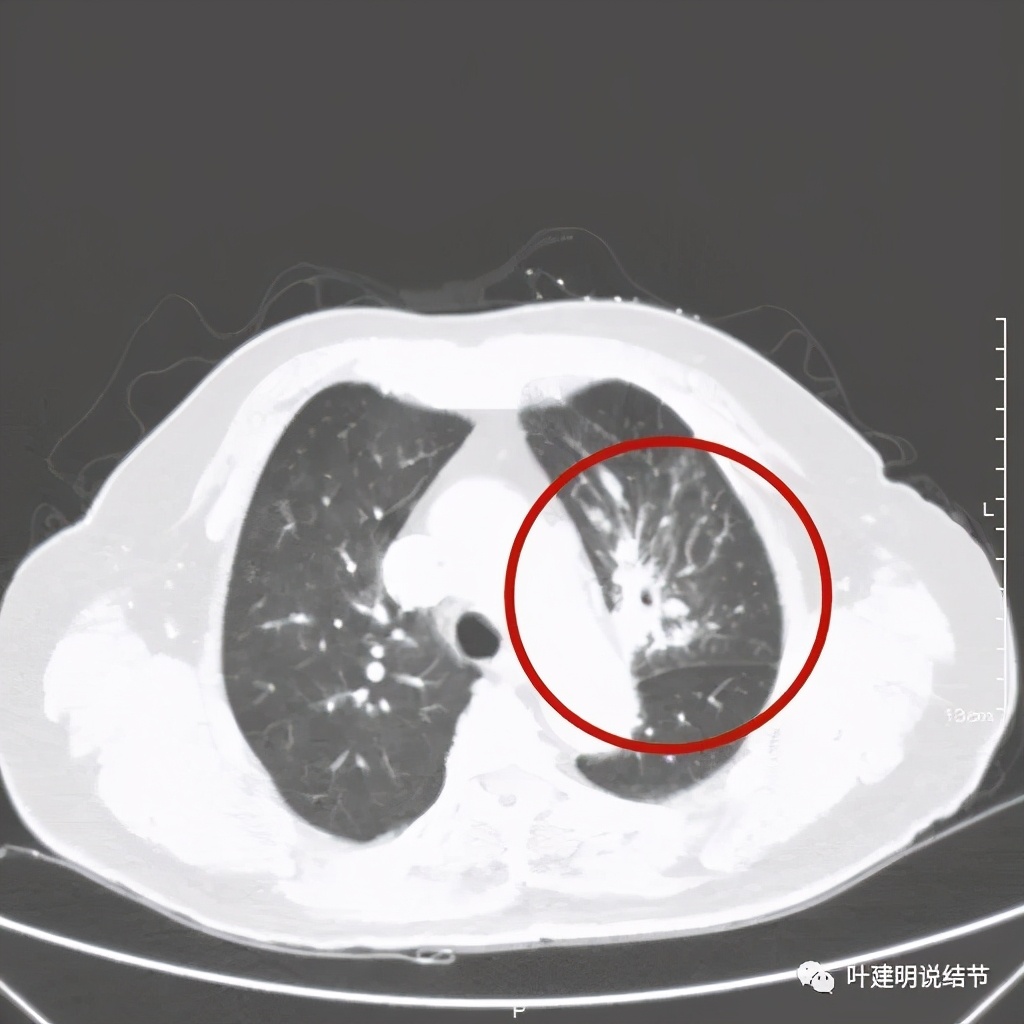

肺窗见原左上叶巨大占位已经明显缩小,甚至几乎不见了!而且上图示左上叶支气管清晰可见,内壁变光滑。纵隔窗增强又是如何的呢?